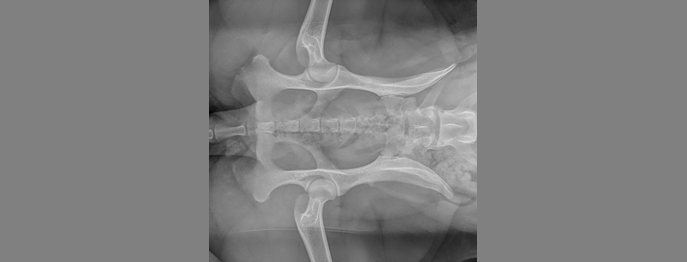

Der Übergangswirbel

beim Hund

Eine häufige Diagnose nach der HD Beurteilung ist ein Übergangswirbel. Jeder redet davon aber was ist das eingentlich? Warum ist ein zusätzlicher Lenden- oder Sakralwirbel problematisch? Man redet von einer vererbbaren Veränderung. Aber was bedeutet das für diesen Hund und kann eine Erkrankung vermieden werden? Was bringt mir eigentlich ein Röntgenbild? Und braucht es ein MRI oder eine Überweisung zum Neurologen?

Ziel dieses vetinars soll sein den Übergangswirbel mit einem klinischen Hintergrund zu klassifizieren. Welche Erkrankung kann folgen und wie merke ich das klinisch? Weithin wollen wir uns ein paar Insights aus der Behandlung anschauen, wie man früh oder auch später intervenieren kann und ob eine chirurgische aber auch medikamentelle Therapie notwendig ist.